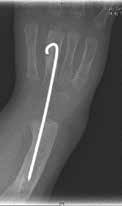

Eine wichtige Voraussetzung vor einer operativen Korrektur der radialen Klumphand ist die Prüfung der Ellenbogenbeweglichkeit (Abb. 8). Ist diese nicht gegeben, kann nach Korrektur gegebenenfalls der Mund zur Nahrungsaufnahme nicht mehr erreicht werden. Bei Vorhandensein einer Kontraktur wird zunächst ein Fixateur externe zur radialen Dehnung und schrittweisen Distraktion angelegt. Es folgt die eigentliche Operation mit Zentralisation der Handwurzel über der Ulna, unterstützt von einem Kirschner-Draht, der nach einigen Monaten wieder entfernt wird. Eine Cast- und später eine Lagerungsschiene werden angepasst, um das Rezidivrisiko zu vermindern (Abb. 9a–e).